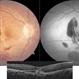

- healed choroiditis, seconadry cnvm

- The image depicts montage color photograph as well as montage fluorescine angiography image of healed multifocal choroiditis with seconadory subfoveal cnvm and subretinal haemorrhage in a 28 years old female patient